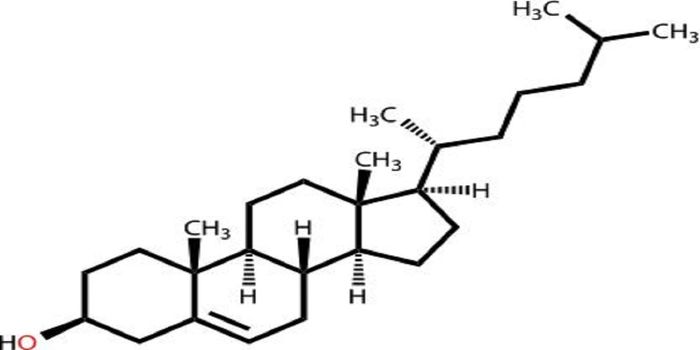

APR 20, 2016Health & MedicineFor atherosclerosis patients who experience a wide range of side effects to cholesterol-lowering drugs, an alternate opt ...